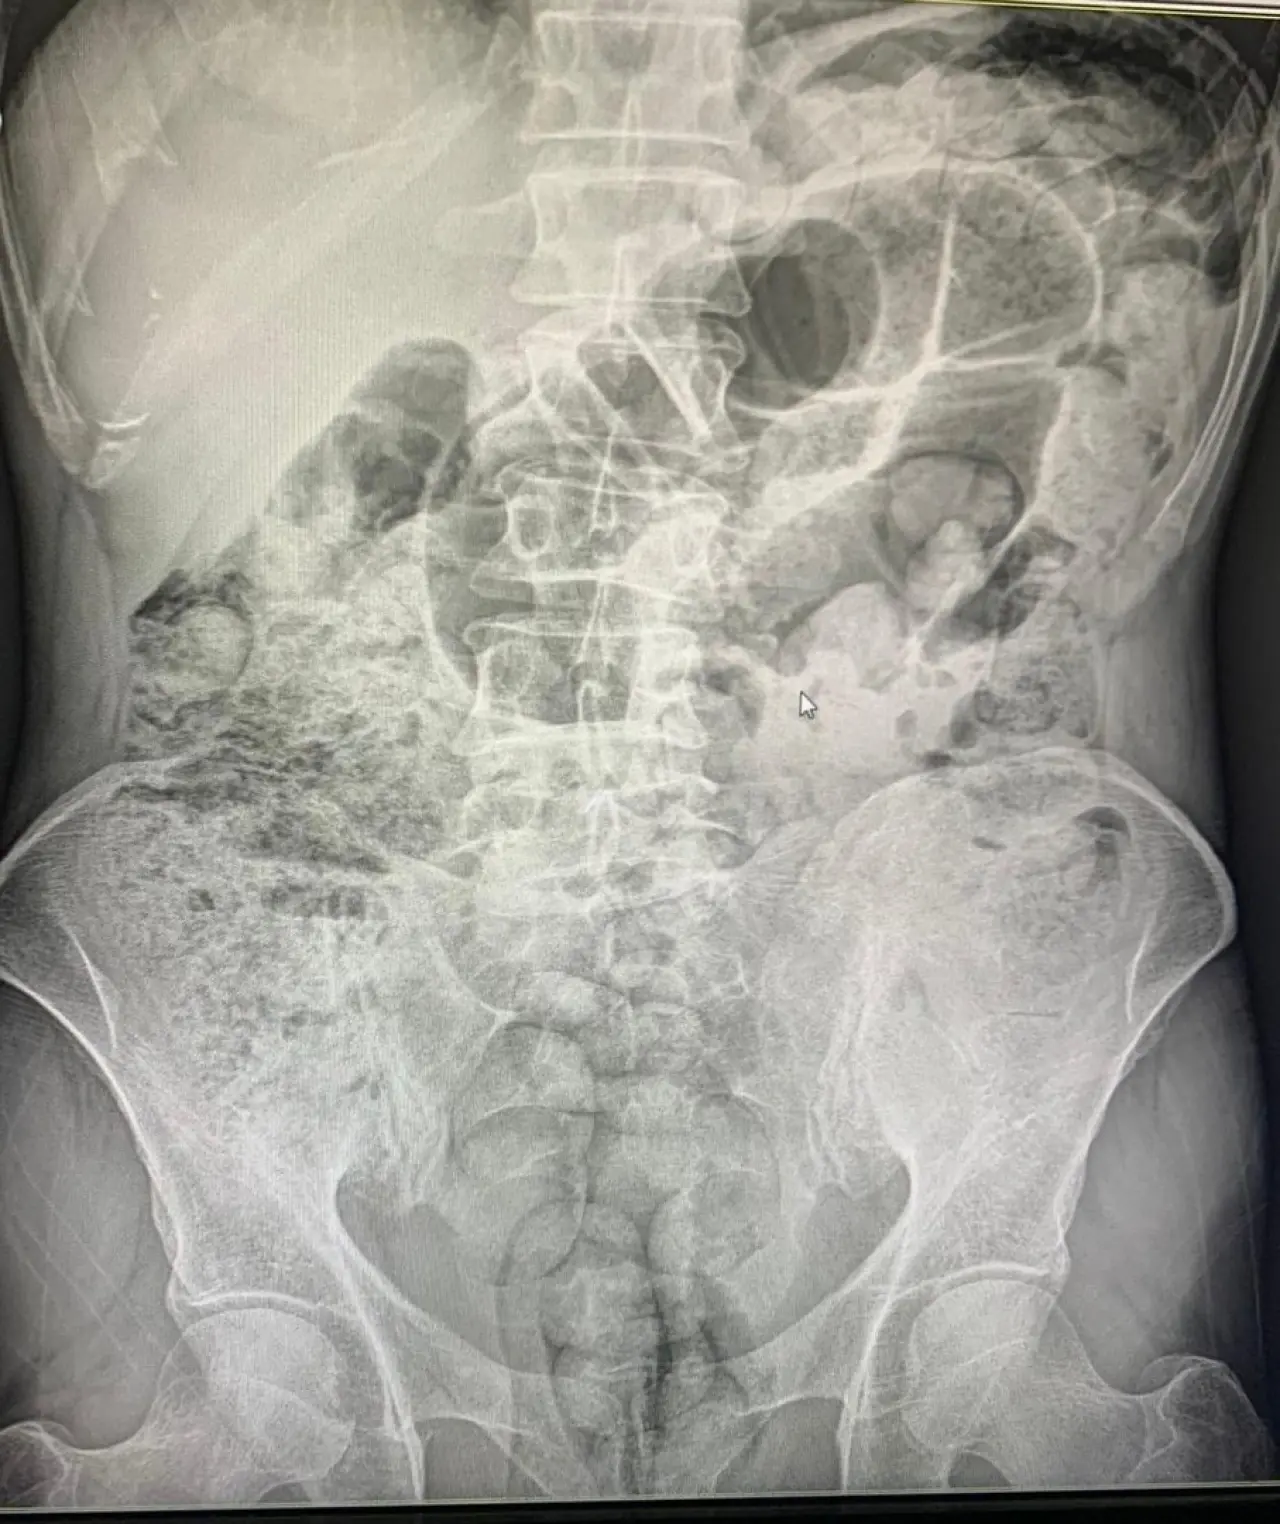

Baykan'daki polis uygulama noktasında durdurulan araçlarda, İran uyruklu 3 kadın ve 1 erkek yakalandı. Şahıslar uyuşturucuyu özel yöntemlerle midelerinde taşıyordu.

Toplam 119 paket halinde 1 kilo 597 gram uyuşturucu madde ele geçirildi. Zanlılar, mahkeme kararıyla tutuklanarak cezaevine gönderildi.